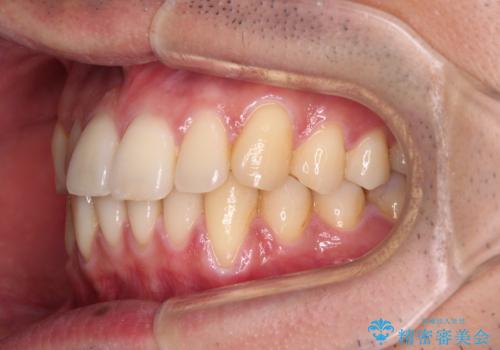

ワイヤー装置での上下前歯の部分矯正

部分矯正は咬み合わせが不安定になったり、スペースができてしまったりと、適用となる患者様は極めて限られますが、こちらの方はスムーズに治療を終えることができました。